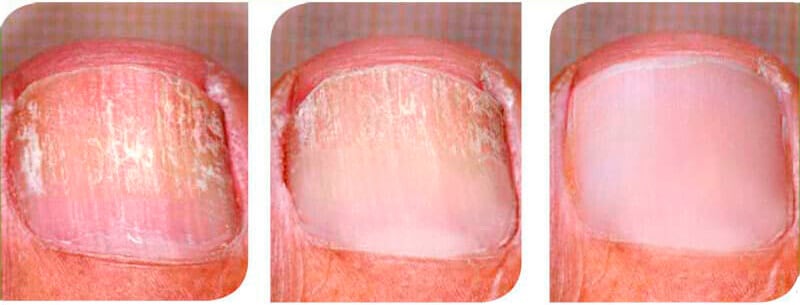

3. Restaura rápidamente las uñas, cura heridas y grietas.

Inicio del tratamientoDos semanas después de comenzar el tratamiento.Cuatro semanas después de iniciar el tratamiento